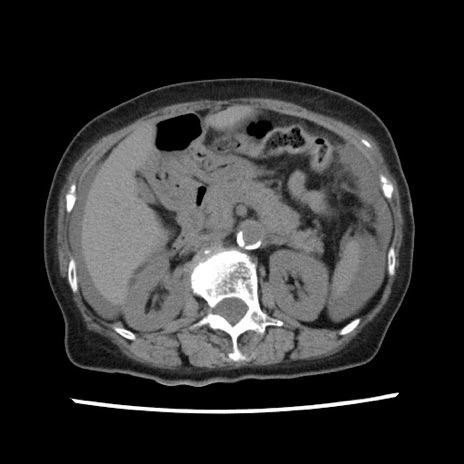

冠状断像

【症例】80歳代女性

【主訴】腹痛

【現病歴】8時間前から腹痛あり来院。

【既往歴】糖尿病、脂質異常症、子宮体癌にて子宮全摘術

【身体所見】意識清明・会話良好だが腹痛で苦悶様、全腹部にわたって反跳痛と圧痛あり

【データ】WBC 13600、CRP 0.14、LDH 224、CK 90